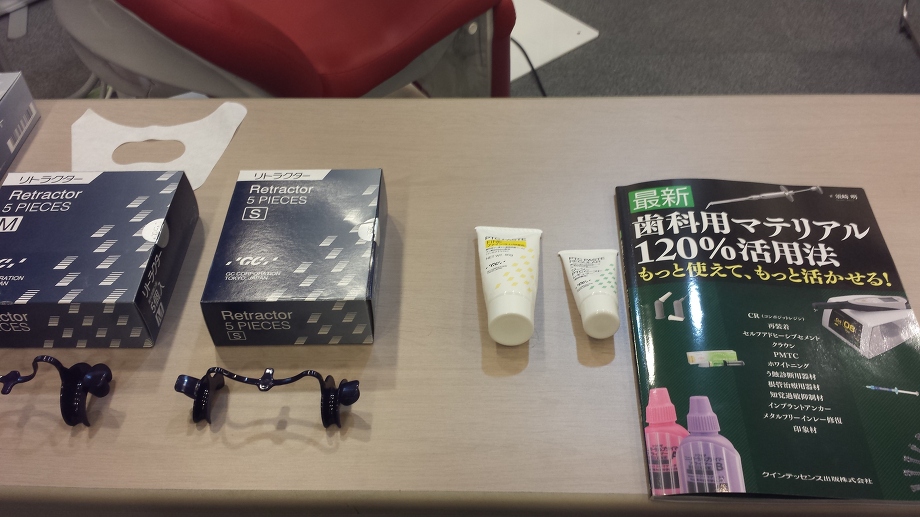

![]() 私たち女性スタッフも、患者様と同じ視点でお話しさせていただけるよう、日々の

私たち女性スタッフも、患者様と同じ視点でお話しさせていただけるよう、日々の![]() 診療のアシストや、歯科や接遇マナーの勉強会

診療のアシストや、歯科や接遇マナーの勉強会![]()

![]() に参加して「わかりやすいことばでの説明」を患者の皆様方にお答えできるように心がけております

に参加して「わかりやすいことばでの説明」を患者の皆様方にお答えできるように心がけております![]()